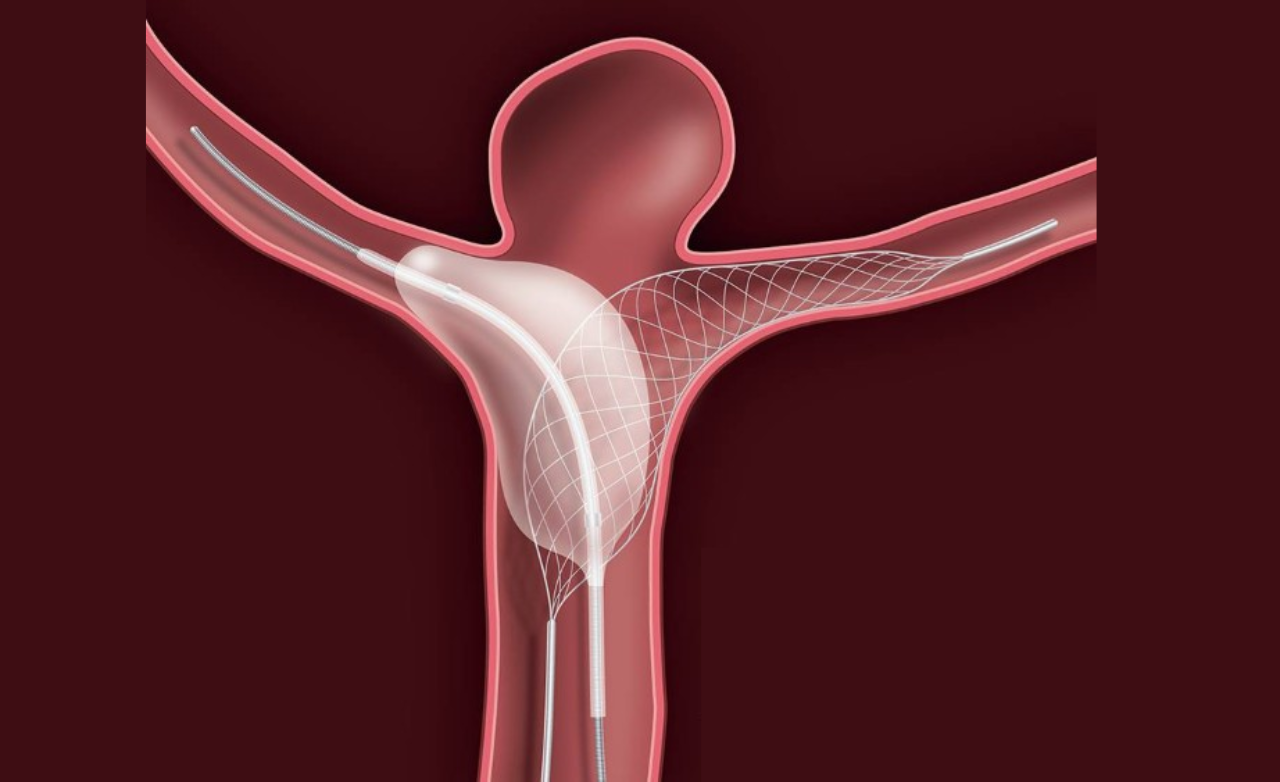

A bulging, weakened blood vessel in the brain that may rupture, causing life-threatening bleeding, headaches, neurological deficits, or stroke.

Minimally invasive technique using soft coils to block aneurysm flow, preventing rupture and ensuring long-term vascular stability.

Provides support for wide-neck aneurysms, ensuring secure coil placement and safer, more effective treatment.

Enhances treatment by redirecting blood flow away from the aneurysm, promoting gradual healing, improving vessel stability, and ensuring stronger, durable protection against future rupture.

Placed directly inside the aneurysm sac, these devices offer targeted treatment with minimal vessel manipulation for improved safety.